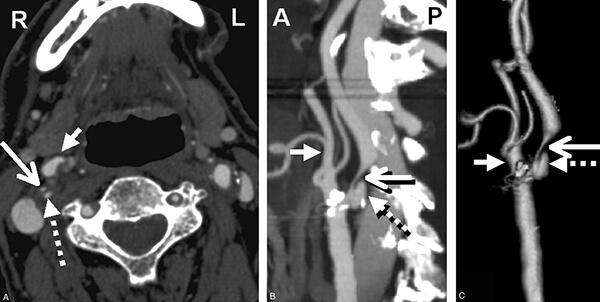

- Η αξονική αγγειογραφία αντίθετα είναι γρήγορη εξέταση και ανιχνεύει εύκολα τις επασβεστώσεις. Ωστόσο δεν μπορεί να διακρίνει ανάμεσα στην εναπόθεση λιπιδίων και την ενδοπλακική αιμορρραγία, παρά μόνο σε μεγάλες πλάκες, ενώ ο ασθενής εκτίθεται σε ιοντίζουσα ακτινοβολία.

Εκτός όμως από το βαθμό της στένωσης της καρωτιδικής πλάκας, υπάρχουν και άλλα στοιχεία που συμβάλλουν στην απόφαση για επεμβατική ή μη θεραπεία της καρωτιδικής νόσου αλλά και την επιλογή της μορφής της επεμβατικής θεραπείας:

- τα μορφολογικά στοιχεία της πλάκας (υφή, σύσταση, φλεγμονή, αιμορραγία) και η πιθανή ανίχνευση μικροεμβόλων, στοιχεία που καθορίζουν την σταθερότητα της.